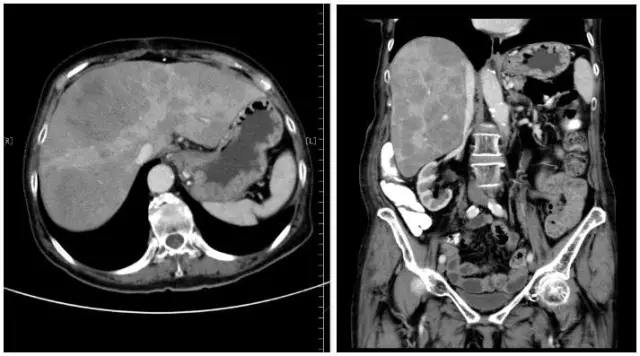

2014年8月复查CT提示肝内病灶继续进展(图1),2014年8月08日99mTc-奥曲肽受体显像提示肝内多发SSR阳性病灶,右腹部偏腹侧SSR阳性病灶,考虑小肠来源NEN 可能性大(图2)。

图1. 2014-8-07腹部增强CT:肝脏体积明显增大,实质内弥漫分布大小不等低密度结节及肿块,部分融合,增强扫描均呈不均匀低强化,最大约82 mm x61mm。考虑转移性。腹腔及腹膜后未见肿大淋巴结。